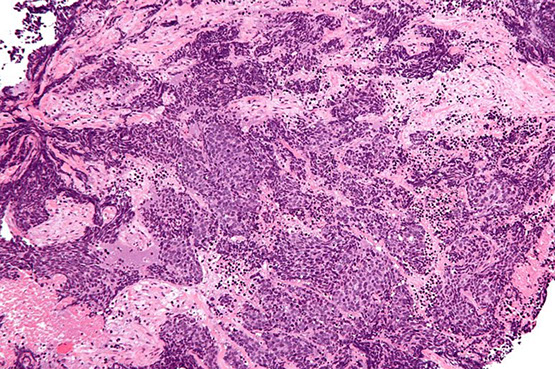

Allergic Fungal Sinusitis

Hypersensitivity rxn to fungal antigens, not an invasive infx

- M=F; MC In kiddos and yound adults

- presents c headaches and obstructive sx

- etiology: aspergillus and diatomaceous fungi

Gross: thick rubbery mucoid material

Micro: thick eosinophilic mucus c layers of degenerated basophilic debris (degenerated eos and neuts)

- sometimes Charcot-Layden crystals

- may see fungal elements on H&E or PAS/GMS

- possibly may not see fungus